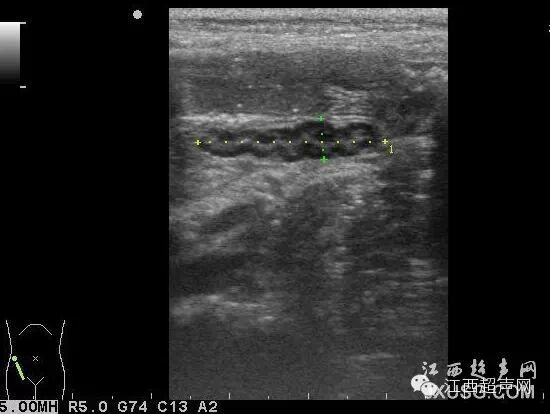

18.心脏左室长轴切面,右室前壁前方低回声的脂肪垫回声易被认为心包积液.

彩超伪像是什么60个超声诊断中容易误诊的正常结构_https://www.jmylbn.com_新闻资讯_第9张